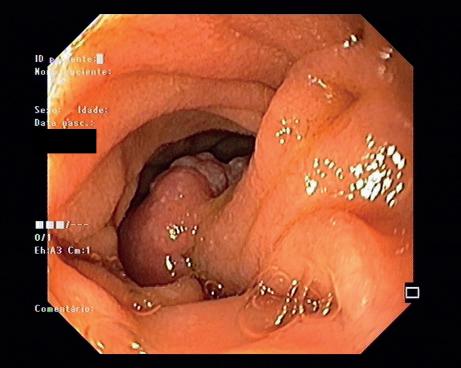

Figura 10.2.5 – Hamartoma: imagens obtidas por BAE que revelam pólipo hamartomatoso no jejuno proximal, que se removeu por ser causa de anemia.